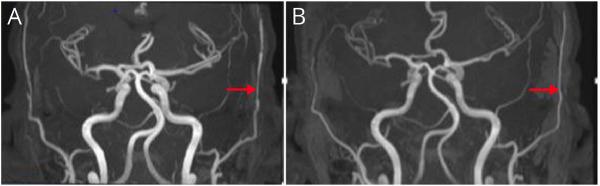

The patient presented with refractory nausea, vomiting, and hiccups that caused weight loss without any other neurologic or clinical symptoms. His MRI scan 15 days later revealed a hyperintense sign on the area postrema with no abnormal diffusion or contrast enhancement, compatible with isolated area postrema syndrome. An extensive workup for inflammation and other etiologies including neuromyelitis optica spectrum disorder (NMOSD), myelin oligodendrocyte glycoprotein antibody disorder, and multiple sclerosis (MS) showed negative results. The patient responded to treatment with methylprednisolone. Two months after the initial clinical manifestation, the patient developed fatigue, headache, and scalp tenderness. He was diagnosed with giant cell arteritis after ultrasonography and biopsy were performed. He responded well to oral glucocorticoids and had only 1 relapse during tapering. He has not had arteritic ischemic optic neuropathy or any new episodes of area postrema syndrome.